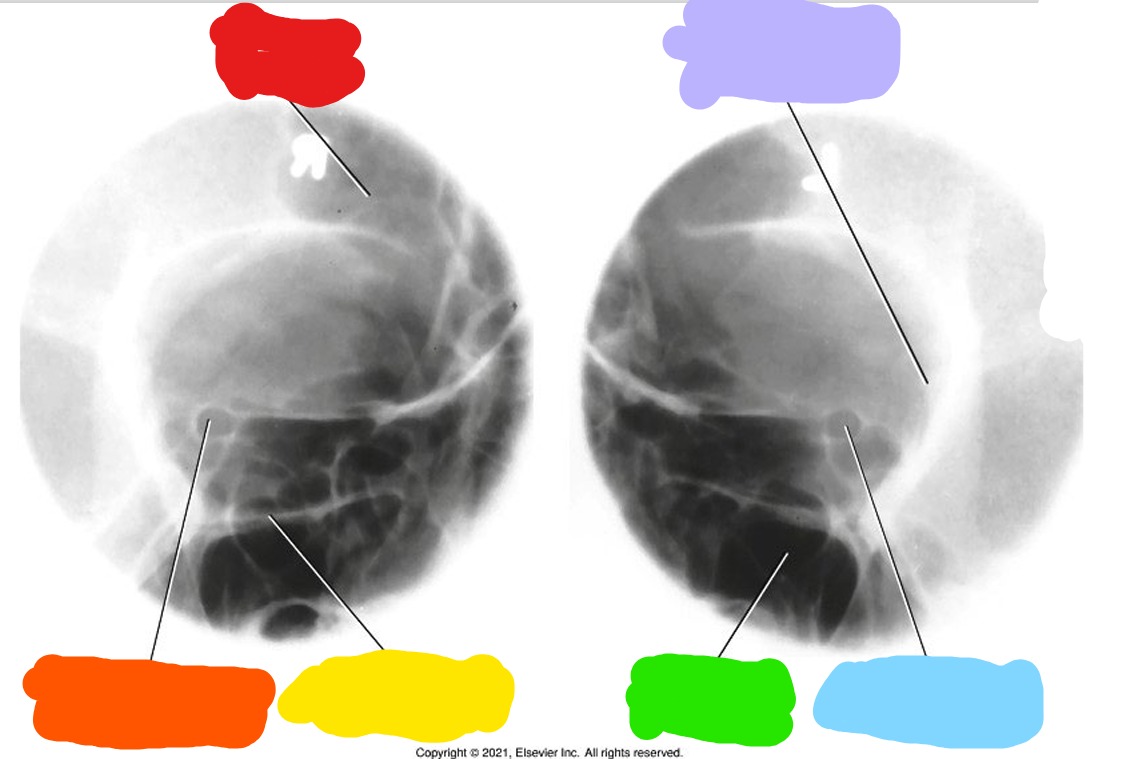

What is Red?

Frontal Sinus

What is Orange?

Optic Foramen and canal

What is Yellow?

Inferior Orbital Rim

What is Green?

Maxillary Sinus

What is Blue?

What is Purple?

Lateral Orbital Margin